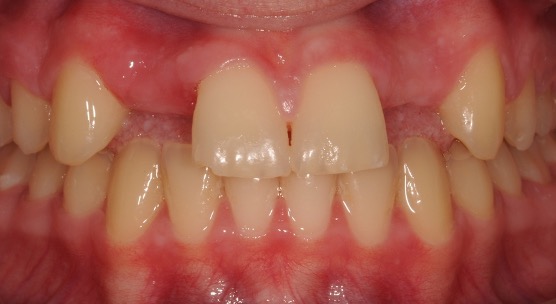

Another case of mild toothwear and discolouration was treated with direct composite bonding.

Composite bonding can also be carried out to close spacing and change the colour of teeth particularly when orthodontic treatment is not desired and tooth whitening has been attempted.